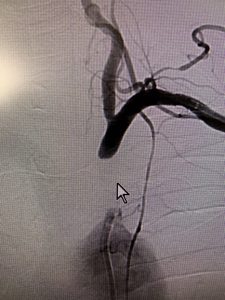

写真1)は巨大内頸動脈未破裂脳動脈瘤です。

写真①

前脈絡叢動脈をコイルで閉塞させないようにステントを併用(写真2)して完全に脳動脈瘤を閉塞(写真3)しています。

巨大内頸動脈未破裂脳動脈瘤です。

前脈絡叢動脈をコイルで閉塞させないようにステントを併用して完全に脳動脈瘤を閉塞しています。